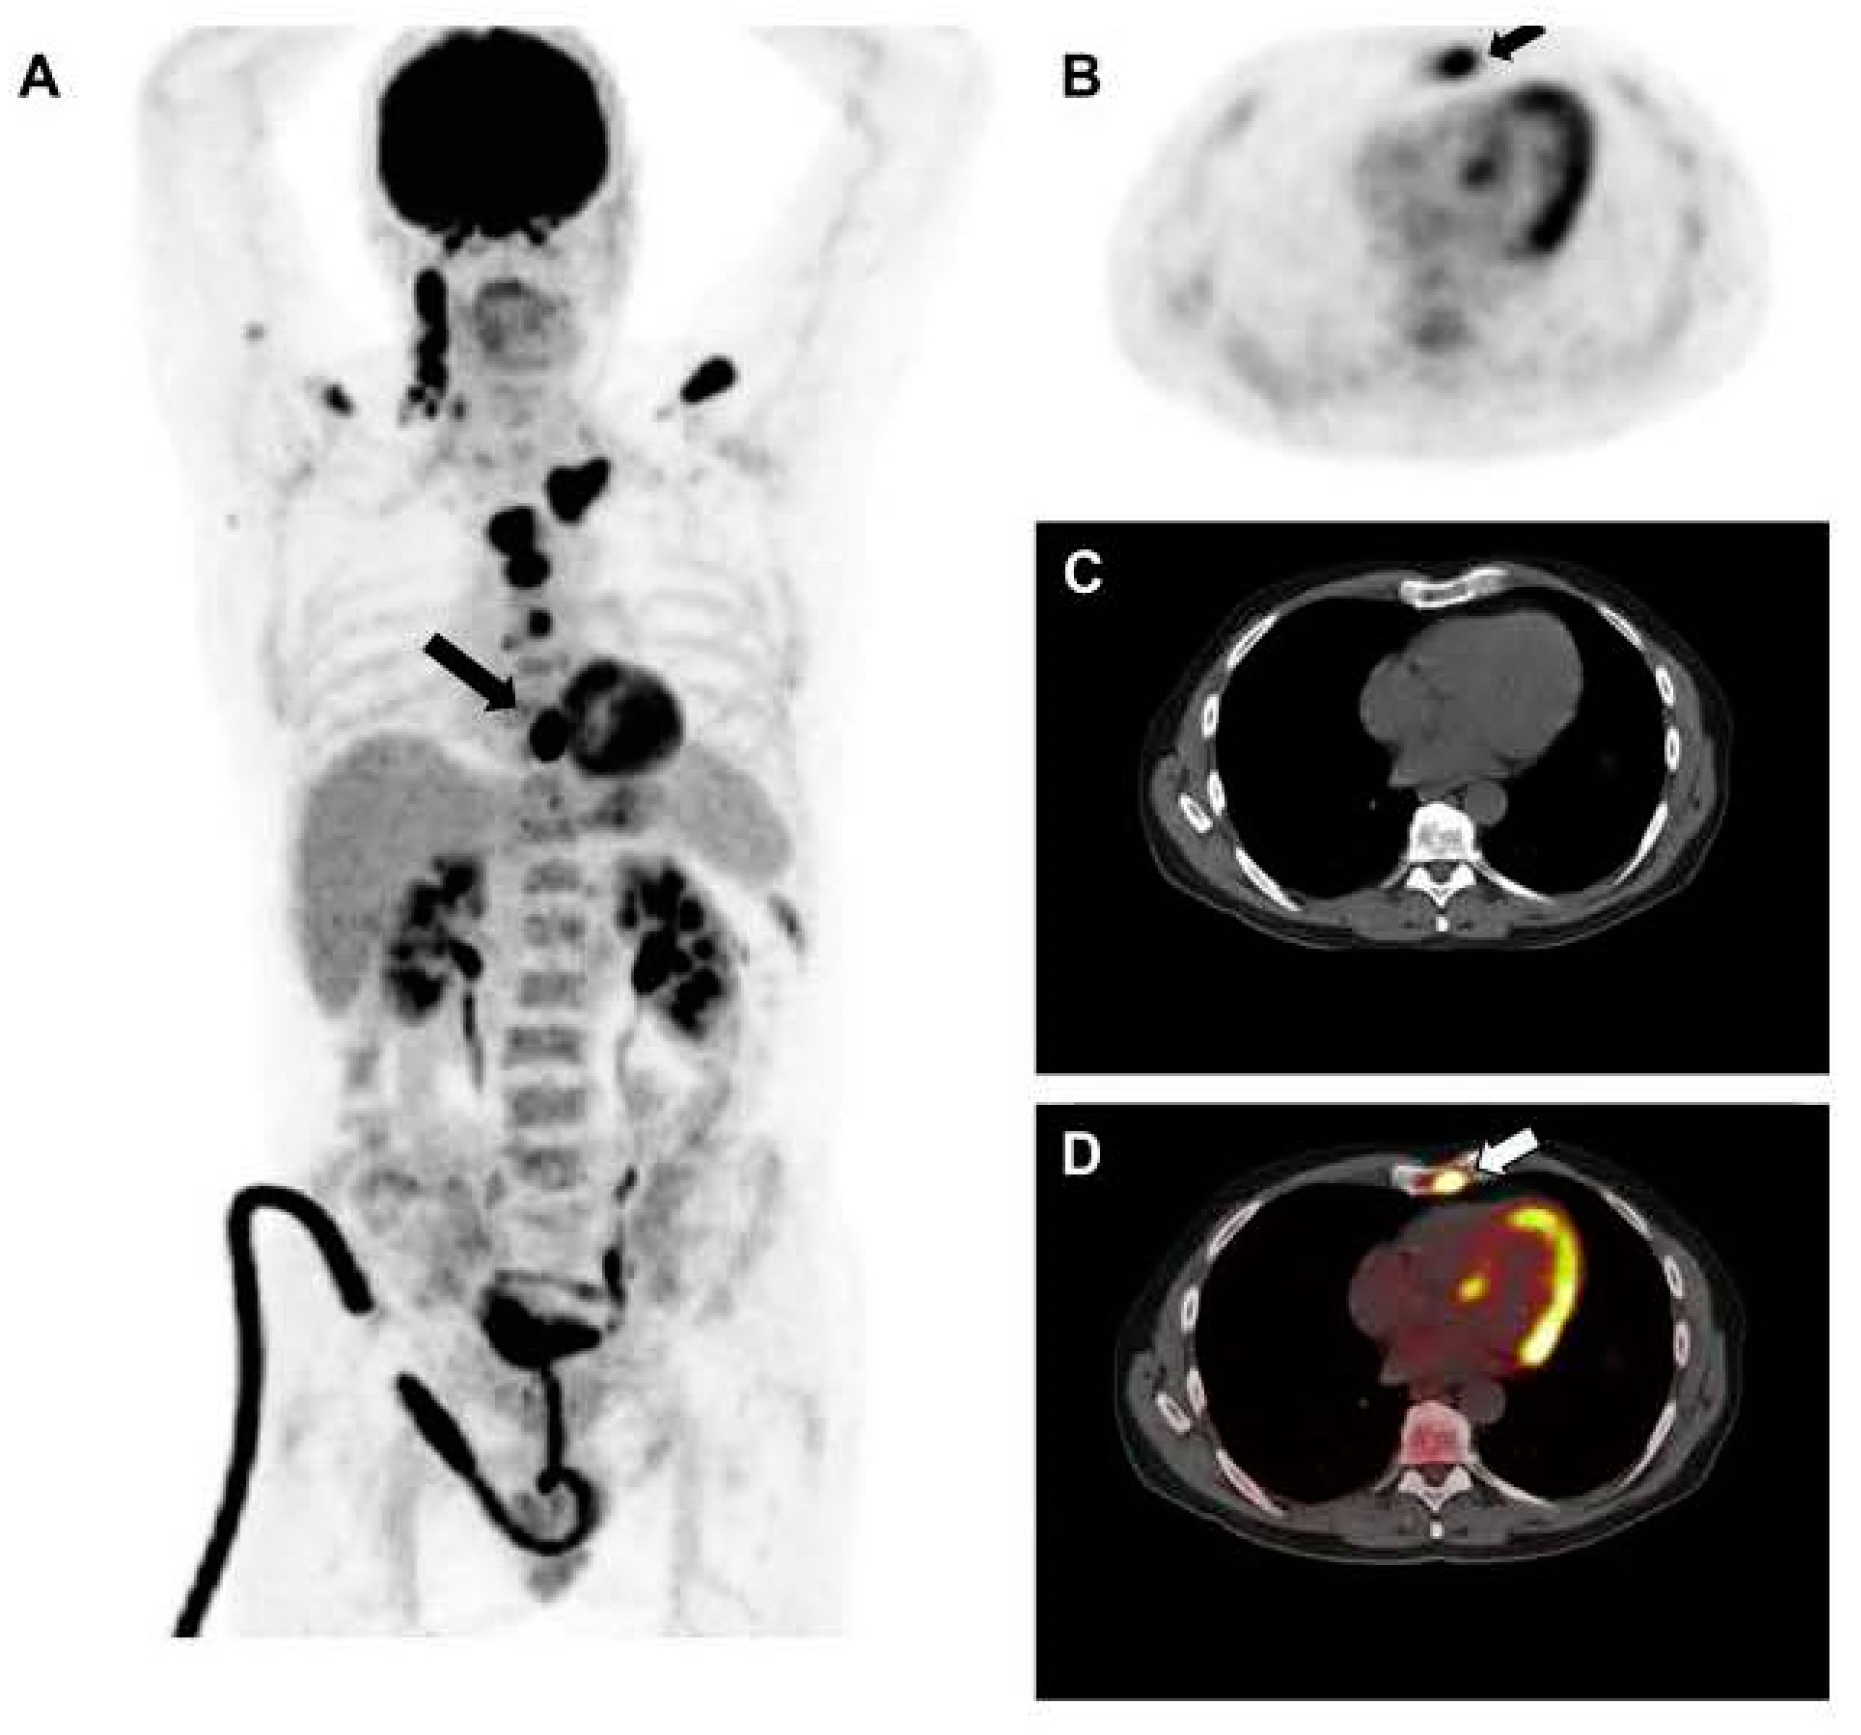

2. Assessment of Bone Disease in MM: An Examination of Osteolytic Lesions

4. Importance of [18F]FDG PET/CT in Assessing Treatment Efficacy

4.2. Assessment of Myeloma Patients after Treatment

5. Identification of Minimal Residual Disease (MRD) in Myeloma